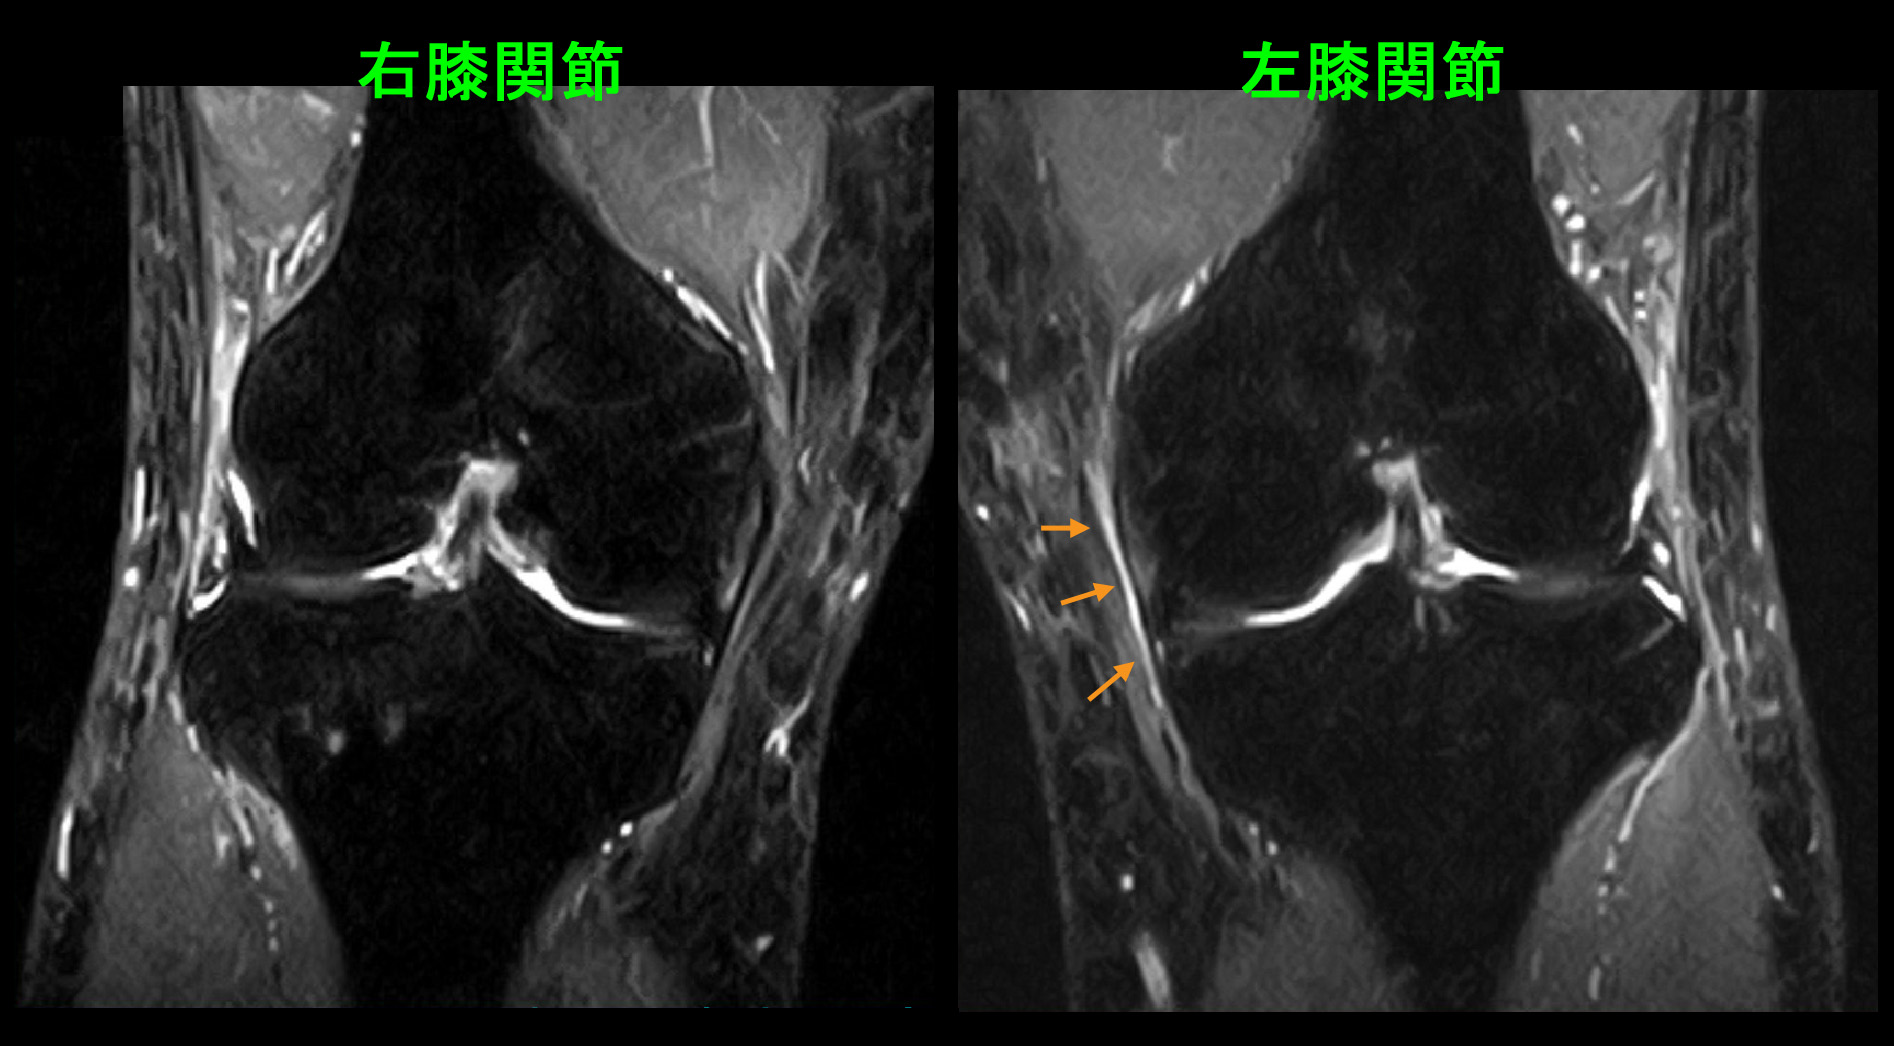

そうであっても思い込みは誤診のリスクを高める可能性につながりますから、両膝のMRI検査を行いました。STIR条件の冠状断(前後像)では左膝の内側に若干の高輝度所見(白い領域)が確認されますが、明瞭で有意とできるほどのものではありません。また、左膝だけを痛がっているわけではなく両側性の訴えですので、症状と一致しません。

43才男 MR1.jpg

PDの冠状断でも矢状断(側面像)でも両膝の半月板には異常を認めません。